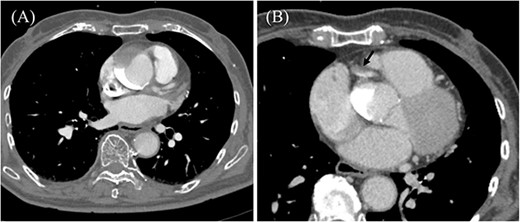

An 85-year-old woman with a history of hypertension and cerebral infarction presented to the emergency department of another hospital with the complaint of temporary loss of consciousness (LOC). Dehydration was suspected to be the cause of LOC; however, CAG was performed to confirm the reason for the mild elevation in creatine kinase and D-dimer levels. While the left coronary system was intact (Fig. 1A), the coronary dissection spread retrogradely from the right sinus of Valsalva to the ascending aorta after injecting contrast into the right coronary artery (RCA). The RCA was completely occluded at the proximal part, and no collateral flow into the RCA was observed (Fig. 1B). Electrocardiography revealed previously undetected ST elevation in leads II, III, and aVF and reciprocal ST depression in leads I, aVL, and V4–6 (Fig. 2). Contrast-enhanced CT confirmed aortic dissection which was localized in the ascending aorta (Fig. 3A). Additionally, RCA occlusion at the proximal portion was suspected (Fig. 3B). The patient was transferred to our institute for further management of the aortocoronary dissection. On arrival, the patient was alert and oriented with close to normal vital signs. Echocardiography showed a normal left ventricular ejection fraction with preserved RV function; however, severe hypokinesis of the inferior wall was noted. Moreover, as the hemodynamic status of the patient gradually deteriorated in the emergency department, we decided to perform an emergency surgery.

Coronary angiography images. (A) Intact left coronary artery without collateral blood supply into the right coronary artery (RCA). (B) Aortocoronary dissection of RCA with total occlusion.